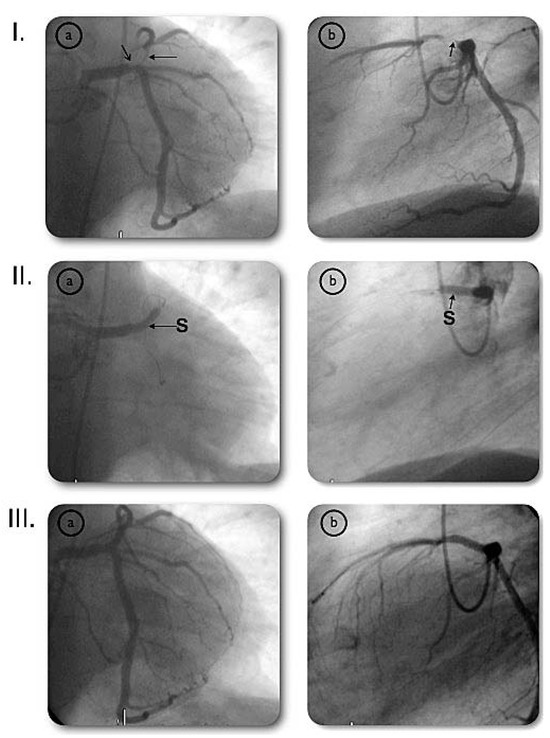

Very Late Stent Thrombosis of a Paclitaxel-Eluting Stent After Left Main Coronary Artery Stenting

by Stéphane Cook, Peter Wenaweser and Christian Seiler

Cardiovasc. Med. 2007, 10(5), 174; https://doi.org/10.4414/cvm.2007.01243 - 25 May 2007

Viewed by 171 Show Figures

Figure 1